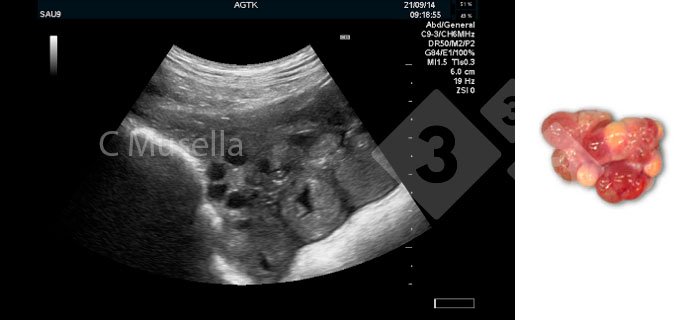

Una sonda con una frequenza di 5 MHz può determinare la gravidanza dal giorno 20-21, mentre una sonda da 7,5 MHz o un buon dispositivo ad ultrasuoni con sonda elettronica può rilevarla dopo 18 giorni.

Il principale vantaggio della diagnosi precoce della gravidanza con una sonda da 7,5 MHz è l'identificazione delle scrofe non gravide e, insieme alla valutazione dello stato ovarico, consente alla scrofa che ritorna di tornare alla produzione prima, evitando l'accumulo di giorni non produttivi; consente inoltre la valutazione individuale del tratto urogenitale per ricercare anomalie fisiopatologiche, velocizzando le decisioni in merito al trattamento o alla eliminazione.